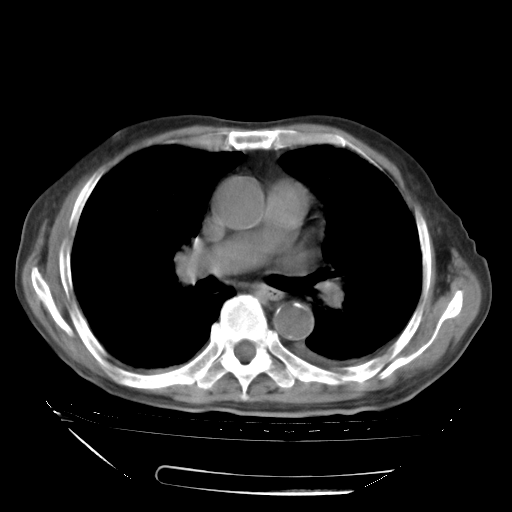

补充下:5月9日胸部CT:似乎已见双下肺胸腔积液了,鉴于目前有下肢水肿,肝功示:白蛋白低,应注意多浆膜腔积液(漏出液可能大?),需注意!

甲强龙80mg/日+抗结核治疗(异烟肼+利福霉素+乙胺丁醇)10天。复查肺部CT。

治疗10天肺部CT